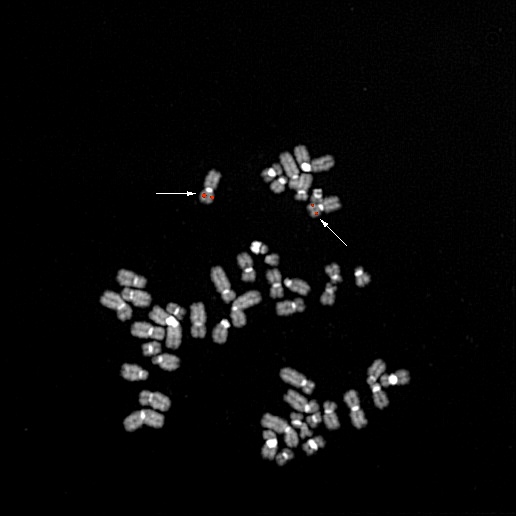

bA59F6